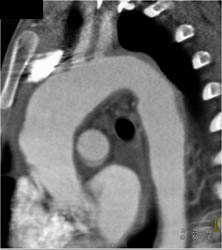

Takayasu's Arteritis